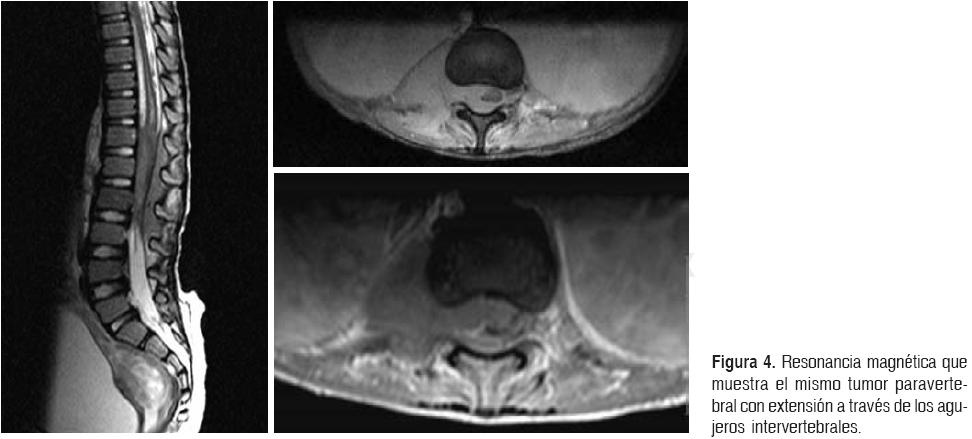

RMN columna: es la prueba de elección. Tiene

una elevada sensibilidad y especificidad, alcanzando una precisión diagnóstica

del 95%. Se recomienda realizar RMN de toda la columna al ser frecuente la

afectación a varios niveles.